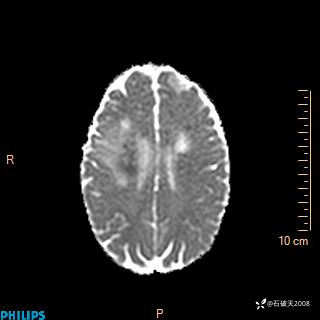

2024.2.21MR

增强冠状位